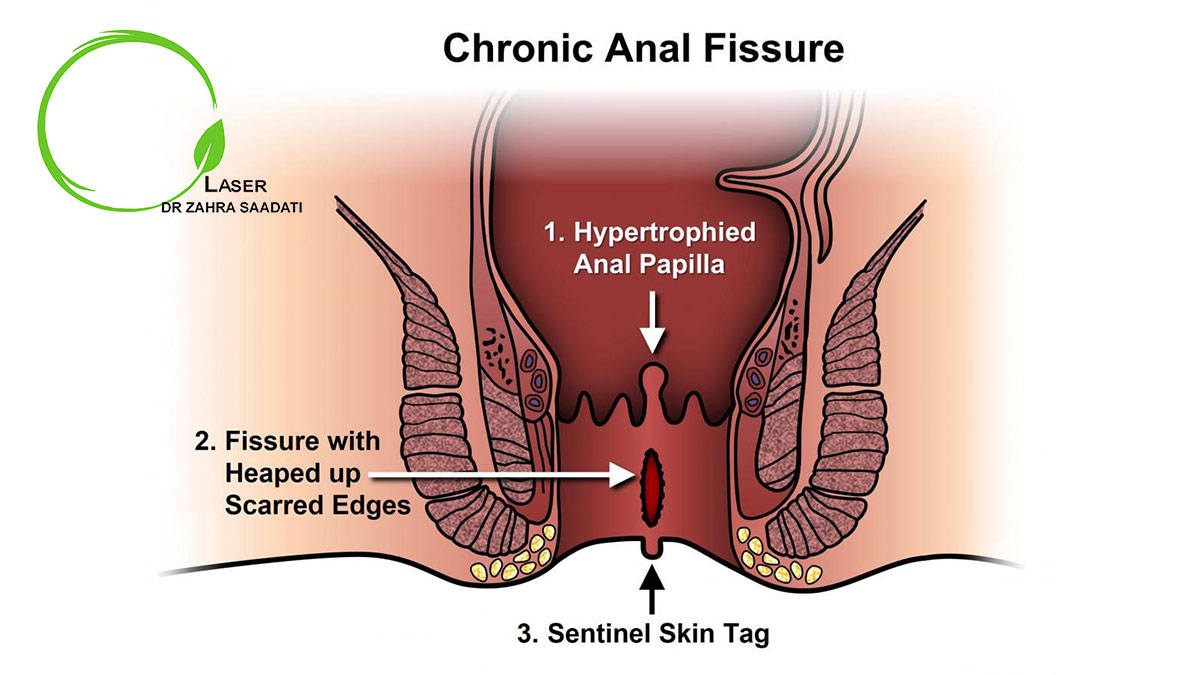

شقاق مزمن مقعد معمولا عود فیشر مقعدی حاد است و همچنین تصور می شود که عبور مدفوع سخت و فشار های مقعدی افزایش یافته و علائم بیش از 6 هفته طول می کشد. شرایط زمینه ای مانند بیماری التهابی روده، سل، اچ آی وی، سرطان مقعد و یا جراحی قبلی مقعد، عوامل مستعد کننده برای هر دو نوع شقاق مقعدی می باشند. تقریبا 40٪ از بیمارانی که با شقاق حاد مواجه می شوند بیماری آن ها به شقاق مزمن تبدیل خواهد شد.

بیمارانی که دچار شقاق مزمن هستند، سابقه ای از درد مقعدی دردناک با خونریزی مستقیم یا بدون خونریزی دارند که طی چند ماه تا احتمالا سال ها ادامه دارد. یبوست مرتبط با آن یکی از رایج ترین فاکتور های شقاق مزمن است و بیماران سابقه طولانی مدفوع سخت را ارائه می دهند. بیماران مبتلا به بیماری هایی از قبیل بیماری کرون، بعضی اوقات، سابقه درد مزمن را طی دفع گزارش می دهند که به طور مداوم احساس می شود.

در شقاق مزمن مقعد ممکن است یک پارگی بزرگ و عمیق کافی باشد تا نقص عضلانی اسفنکتر مقعد را افشا نماید. علاوه بر این، به علت تکرار مجدد آسیب و چرخه بهبودی، گاهی اوقات لبه های ناحیه دچار افزایش حجم شده و ضخیم شدن بافت در انتهای آن می تواند وجود داشته باشد.